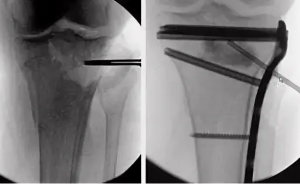

После стабилизации состояния и заживления ран на левой голени (рис. 1) через 72 дня после ранения провели операцию: внеочаговый чрескостный компрессионно-дистракционный остеосинтез (ВЧКДО) по Илизарову левой голени, остеотомия дистального отломка левой большеберцовой кости. Дефект большеберцовой кости — 15 см. На 79-е сутки после ранения начали перемещение фрагмента с целью формирования регенерата и замещения дефекта. На 164-е сутки после ранения (85 суток после остеотомии) для коррекции положения и направления перемещения фрагмента выполнили перемонтаж аппарата Илизарова на левой голени. Продолжили перемещение фрагмента дистального отломка большеберцовой кости (рис. 2).

На 261-е сутки после ранения (182-е сутки после остеотомии) отметили контакт фрагмента и проксимального отломка через зону инвагинации (рис. 3). В целях обеспечения контакта проксимального отломка и перемещаемого фрагмента дистального отломка на 262-е сутки после ранения (183-и сутки после остеотомии) выполнили резекции зоны инвагинации и костно-хрящевого комплекса на торце проксимального отломка и перемещаемого фрагмента, открытую репозицию отломков, перемонтаж аппарата Илизарова. Достигнут контакт торцевых частей проксимального отломка и перемещаемого фрагмента (рис. 4). В последующем проводили компрессию между проксимальным отломком и фрагментом, «воспитание регенерата» методом «аккордеона».